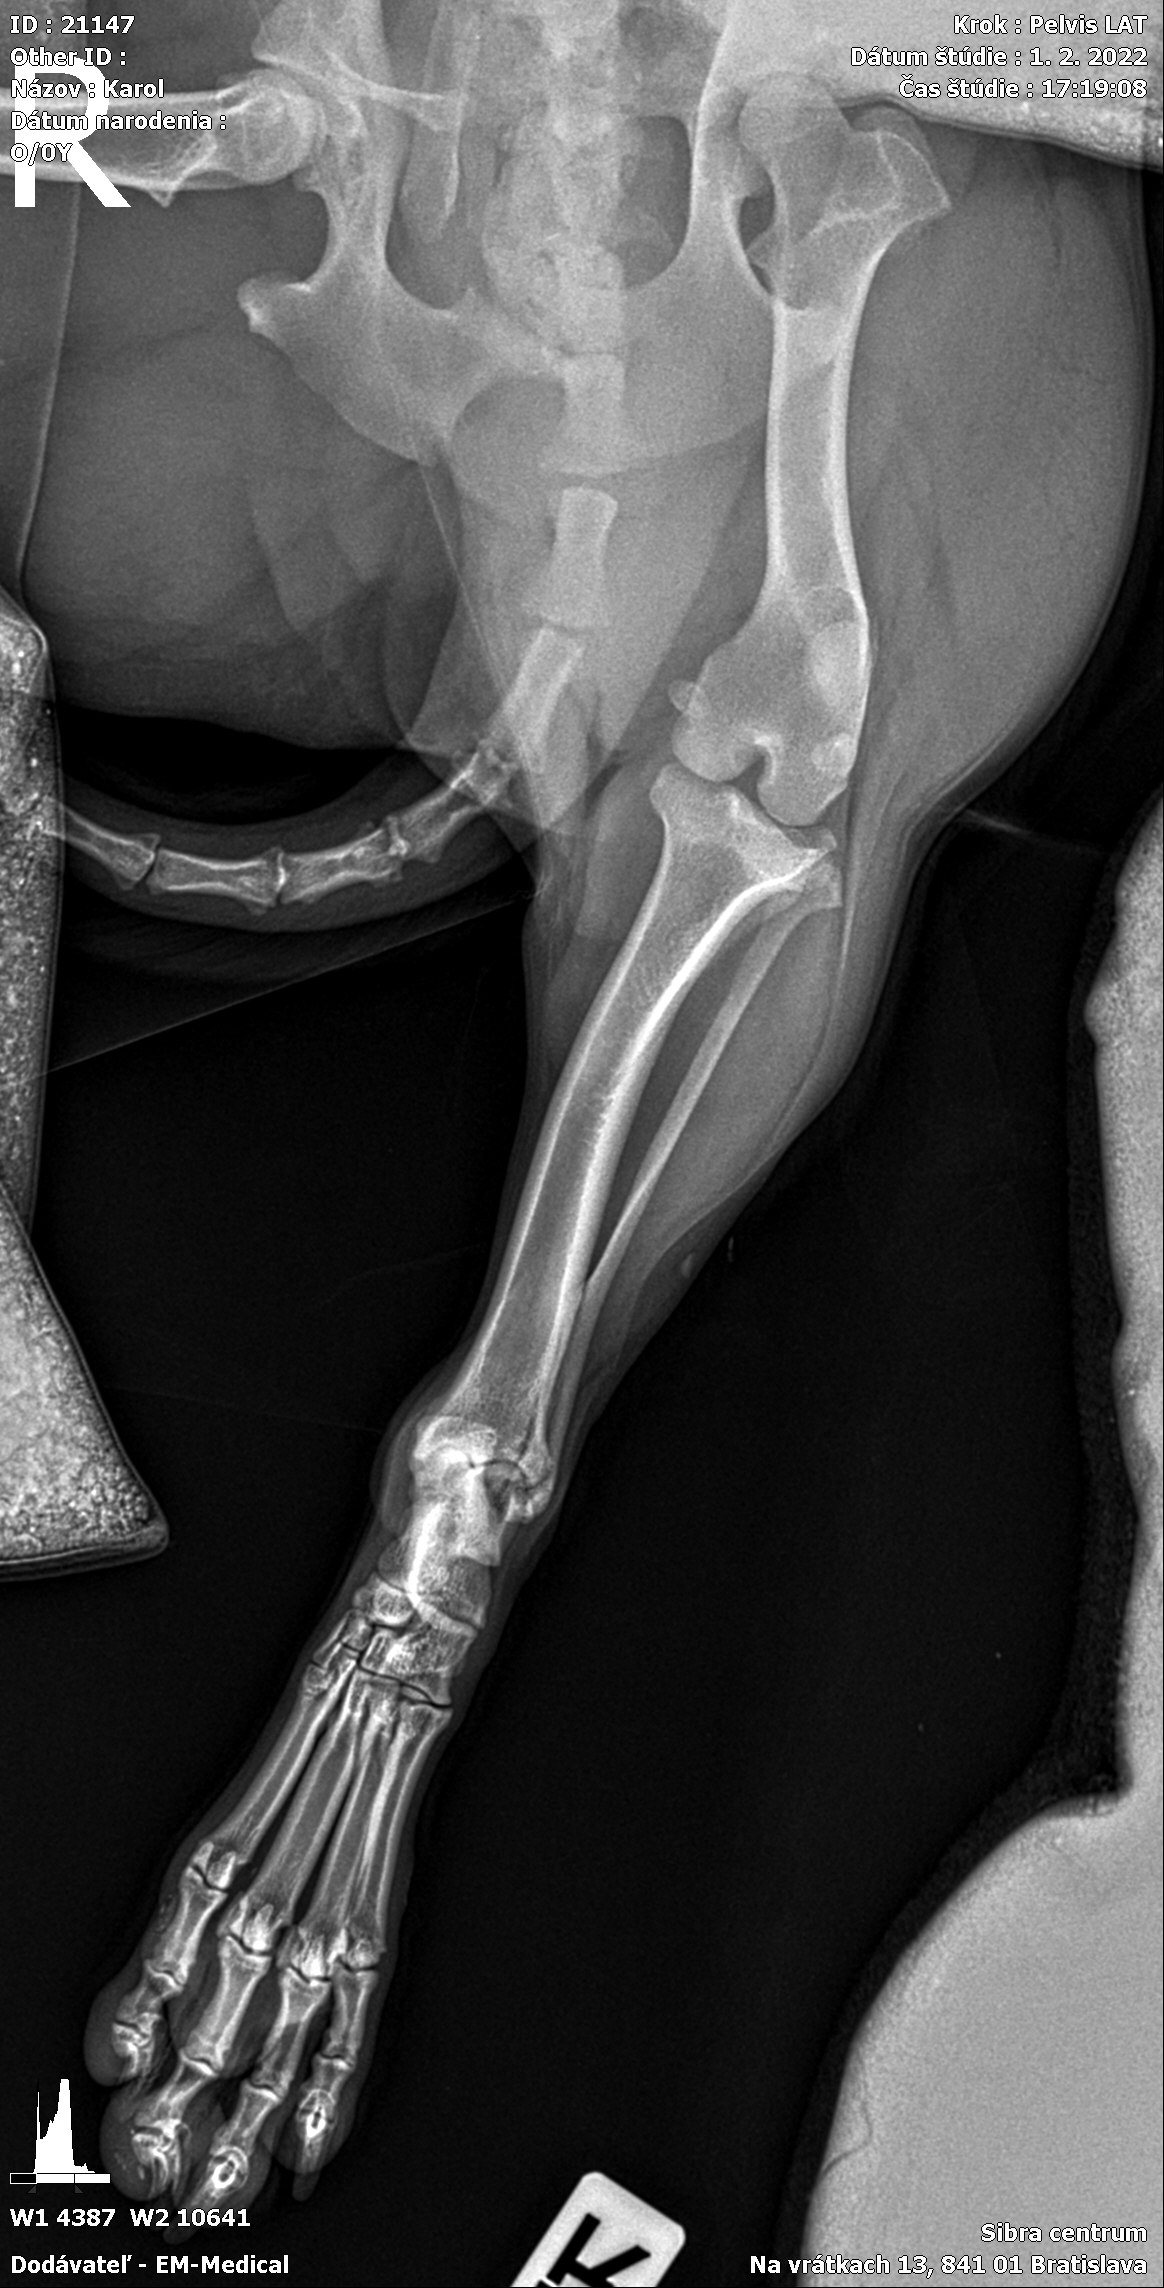

Karola nám doviezla pani, ktorá ho našla, asi jediná dobrá duša, ktorá pri ňom neprešla so zatvorenými očami. Ihneď sme s krpcom utekali na veterinu aby sa zistila závažnosť jeho zranení. Hneď pri prvých RTG snímkoch sa ukázala obojstranná fraktúra panvy, taktiež fraktúra krídla panvy a keby mu to chudákovi nestačilo, do tretice sa objavila zlomenina stavca. Karolko mal neznesiteľné bolesti, ale krásne prečkal vyšetrenie lebo vedel, že je v dobrých rukách a dostáva sa mu pomoci. Po nálezoch sme okamžite kontaktovali neurológiu a ortopédiu na veterinárnej klinike Sibra - centrum veterinárnej medicíny, kde sme dostali hneď termín na príjem.

Karol nemá žiadne neurologické deficity, po ortopedickej operácii bude vedieť behať a bez problémov bude vedieť samostatne cikať a kakať. Po tejto úžasnej správe sme samozrejme dali zelenú náročnej ortopedickej operácii pod vedením MVDr. Vatolíka. Operácia sa podarila na výbornú, Karči je "zoskrutkovaný" a vôbec nič mu nebráni v tom, aby opäť mohol behať a aktívne žiť. Momentálne sa zotavuje po operácii, musí mať prísny kľudový režim. Po vybratí stehov ho čaká hydro- a fyzioterapia, ktorá mu pomôže postaviť sa na nohy. Je to bojovník, veľmi sa chce uzdraviť a v jeho očkách je dokonale vidieť, že už kuje plány čo všetko zameškané bude musieť dobehnúť.